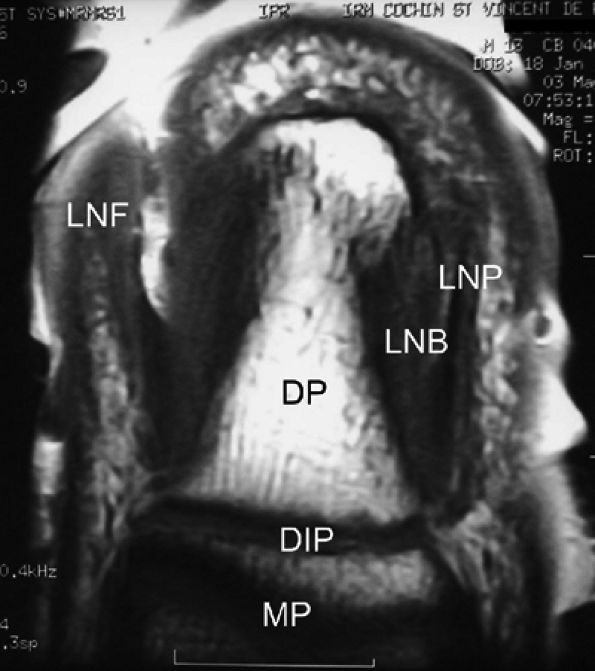

|

FIGURE 11.113 ● Coronal anatomy of the nail unit on T1-weighted images. MP, middle phalanx; DP, distal phalanx; DIP, distal interphalangeal joint; LNB, lateral nail bed; PNF, proximal nail fold; LNP, lateral border of nail plate.

FIGURE 11.108 ● Axial anatomy of the nail unit. (A) Distal interphalangeal joint. (B) Matrix area. (C) Photomicrograph of the matrix area with hematoxylin and eosin staining. (D) Nail bed area. ET, extensor tendon; PNE, posterior nail fold; CL, collateral ligament; MP, middle phalanx; VP, volar plate; FDP, flexor digitorum tendon; MPL; matricophalangeal ligament; NR, nail root; PLNM, posterolateral corners of the nail matrix; SMA; submatrix area; DM; dorsal matrix; IM, intermediate matrix; DP, distal phalanx; P, pulp; LF, ligament of Flint; NBE, nail bed epithelium; NBC, nail bed corium; LNF, lateral nail fold; RU; rima ungualum.